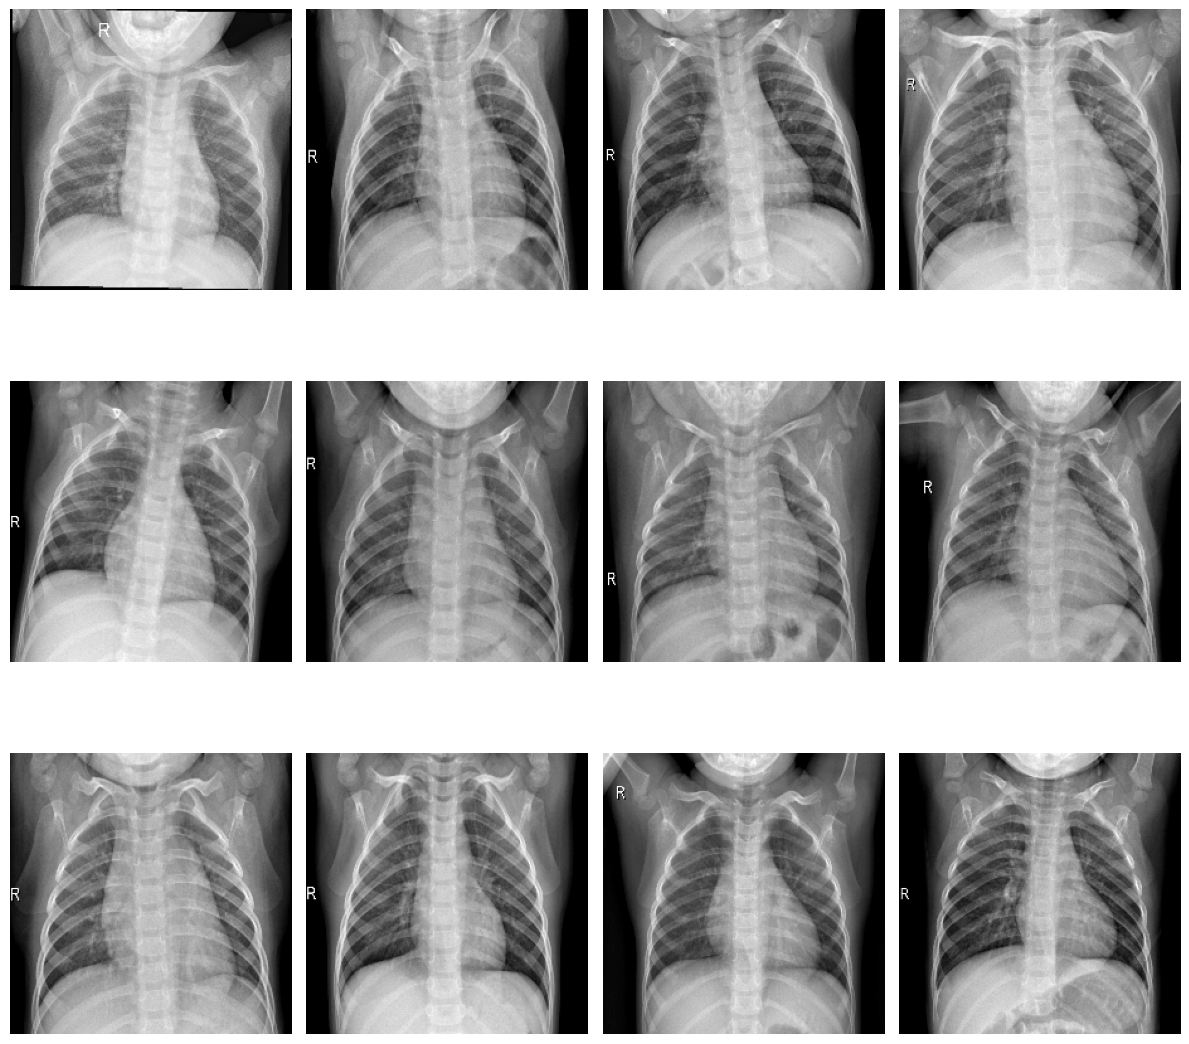

plot_samples(train_normal, 12, 3, 4, save_as="train_samples_normal.png")

../_images/train_samples_normal.png

Samples of healthy patients in training data